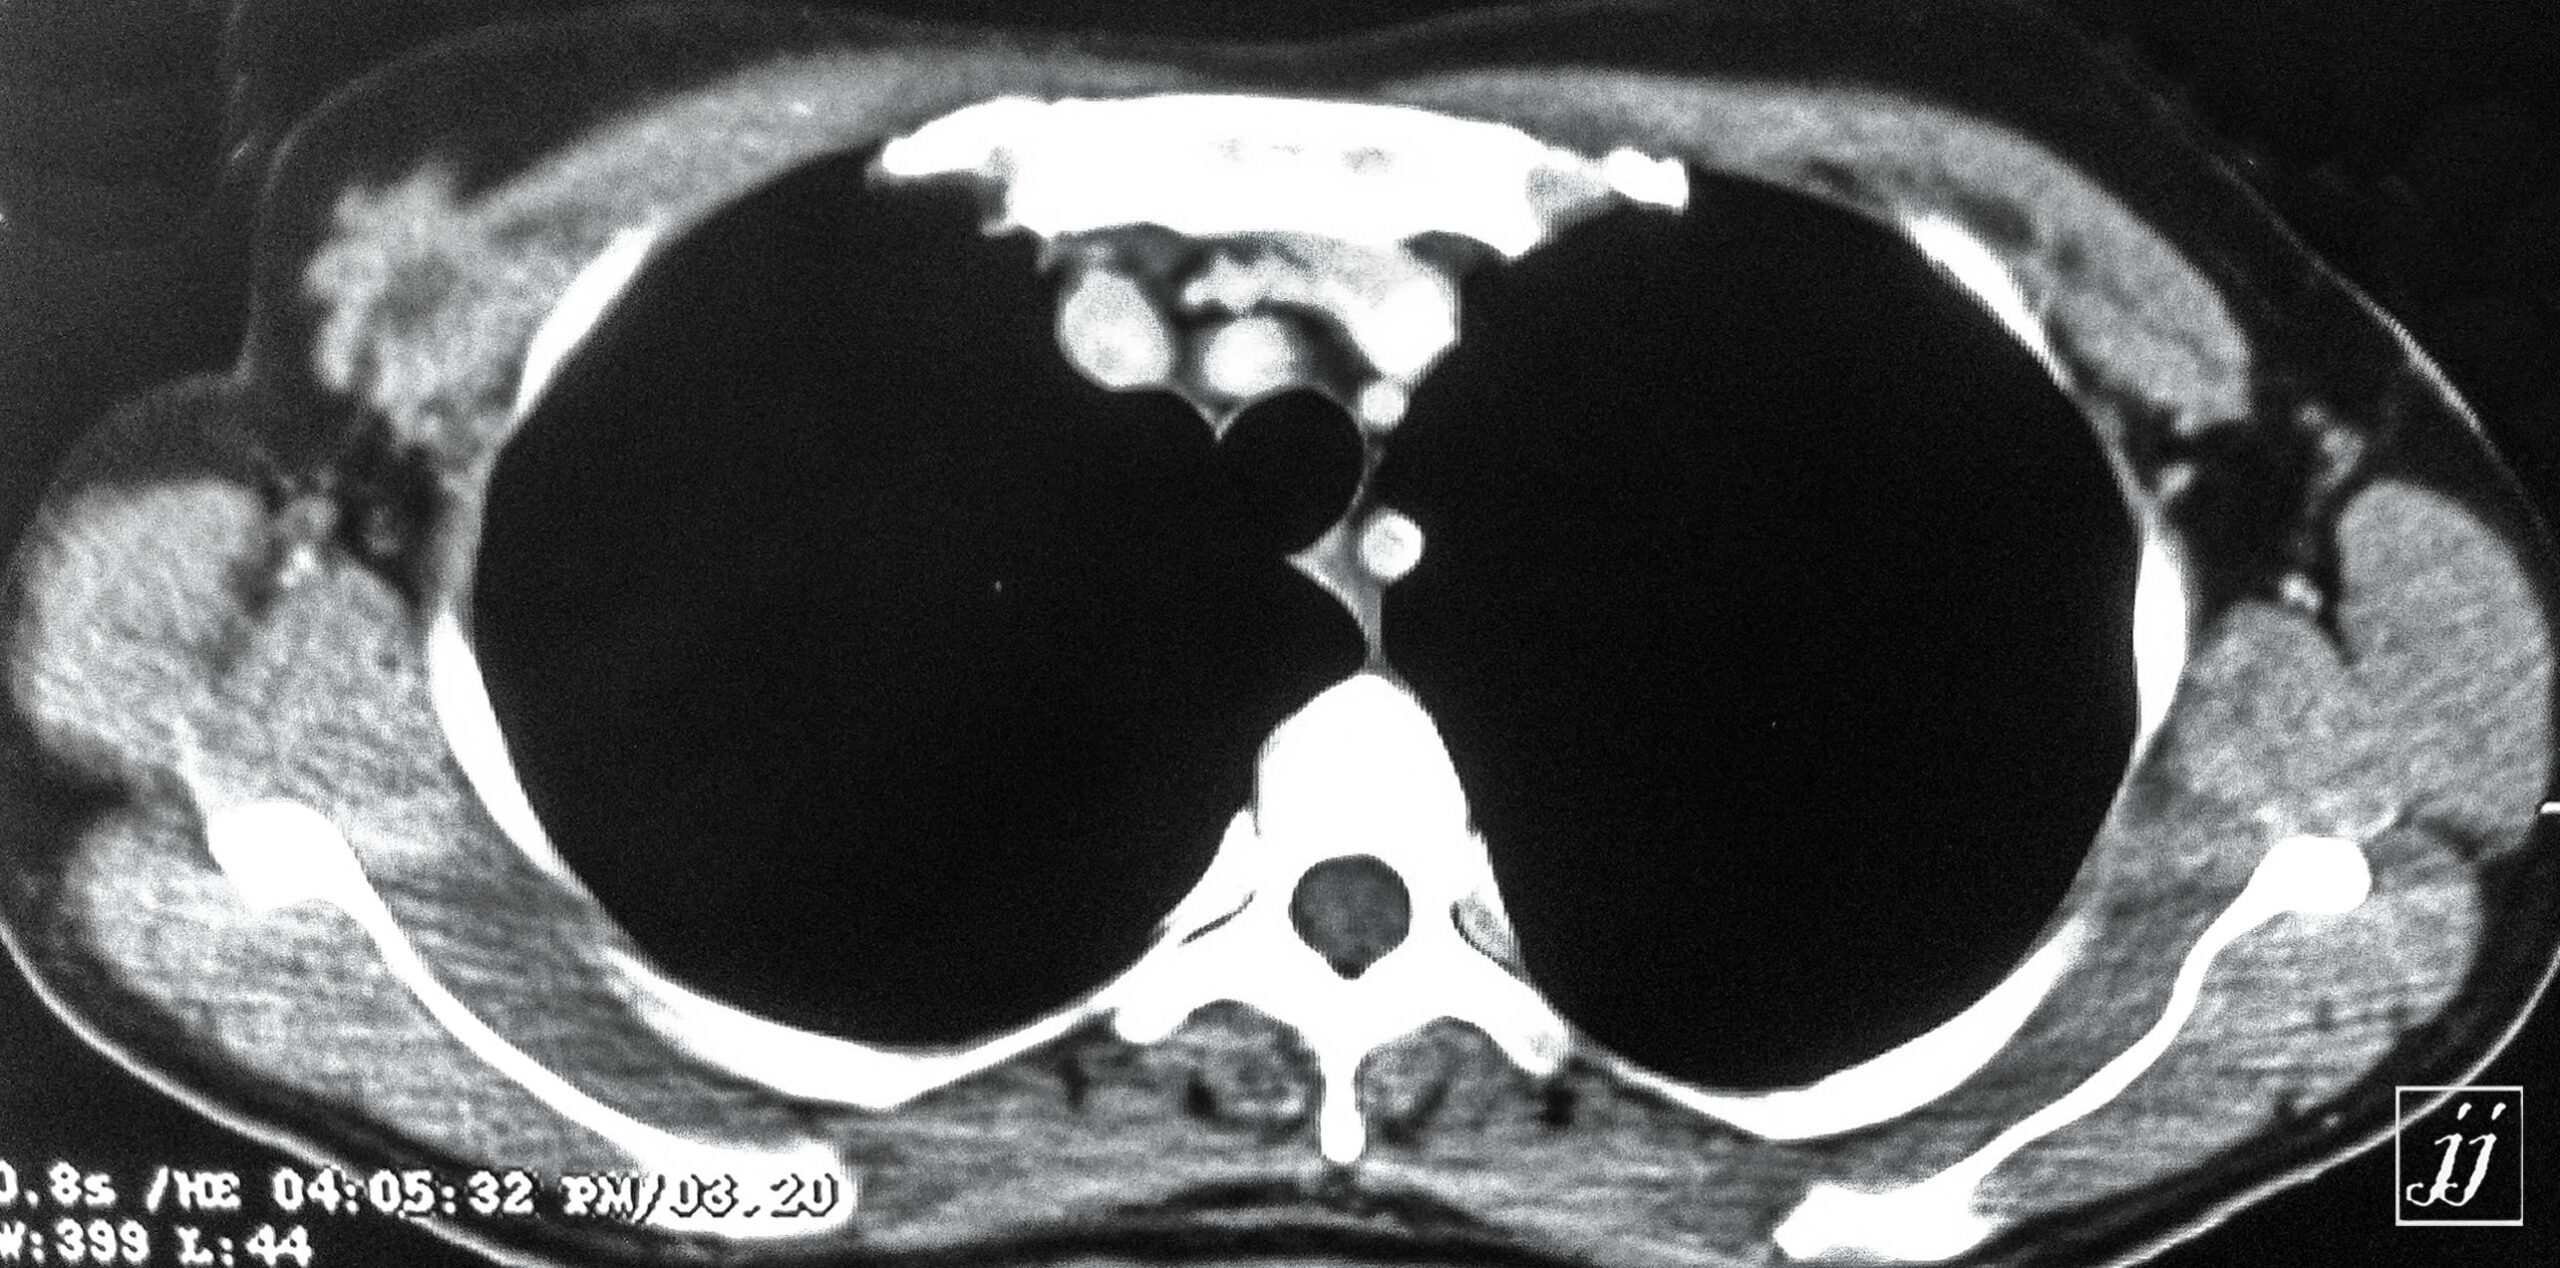

Abdomen- right vectoralis muscle mass (2)